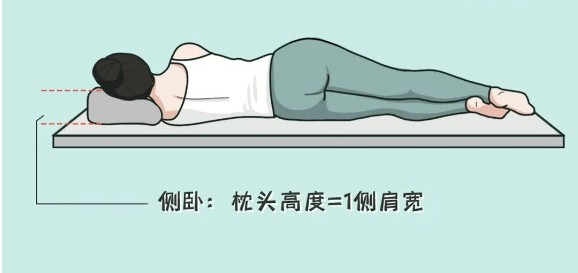

枕头应该将颈和头同时支撑,这样有利于颈后部肌肉、韧带的放松,消除疲劳。从颈椎健康讲,最佳睡眠姿势是仰卧,能最好地维持颈椎自然弧度。

如果平躺时,枕头下陷一部分刚好可以支撑住颈曲就可以了。习惯侧睡的人,枕头高度与自己一侧肩宽长度一致为宜。

喜欢侧身睡觉的人,枕头就需稍微硬些,压下去保证脖子和身体平直,让颈部肌肉放松。荞麦枕头很合适,冬暖夏凉,能顺着头部的移动改变形状,非常舒服。